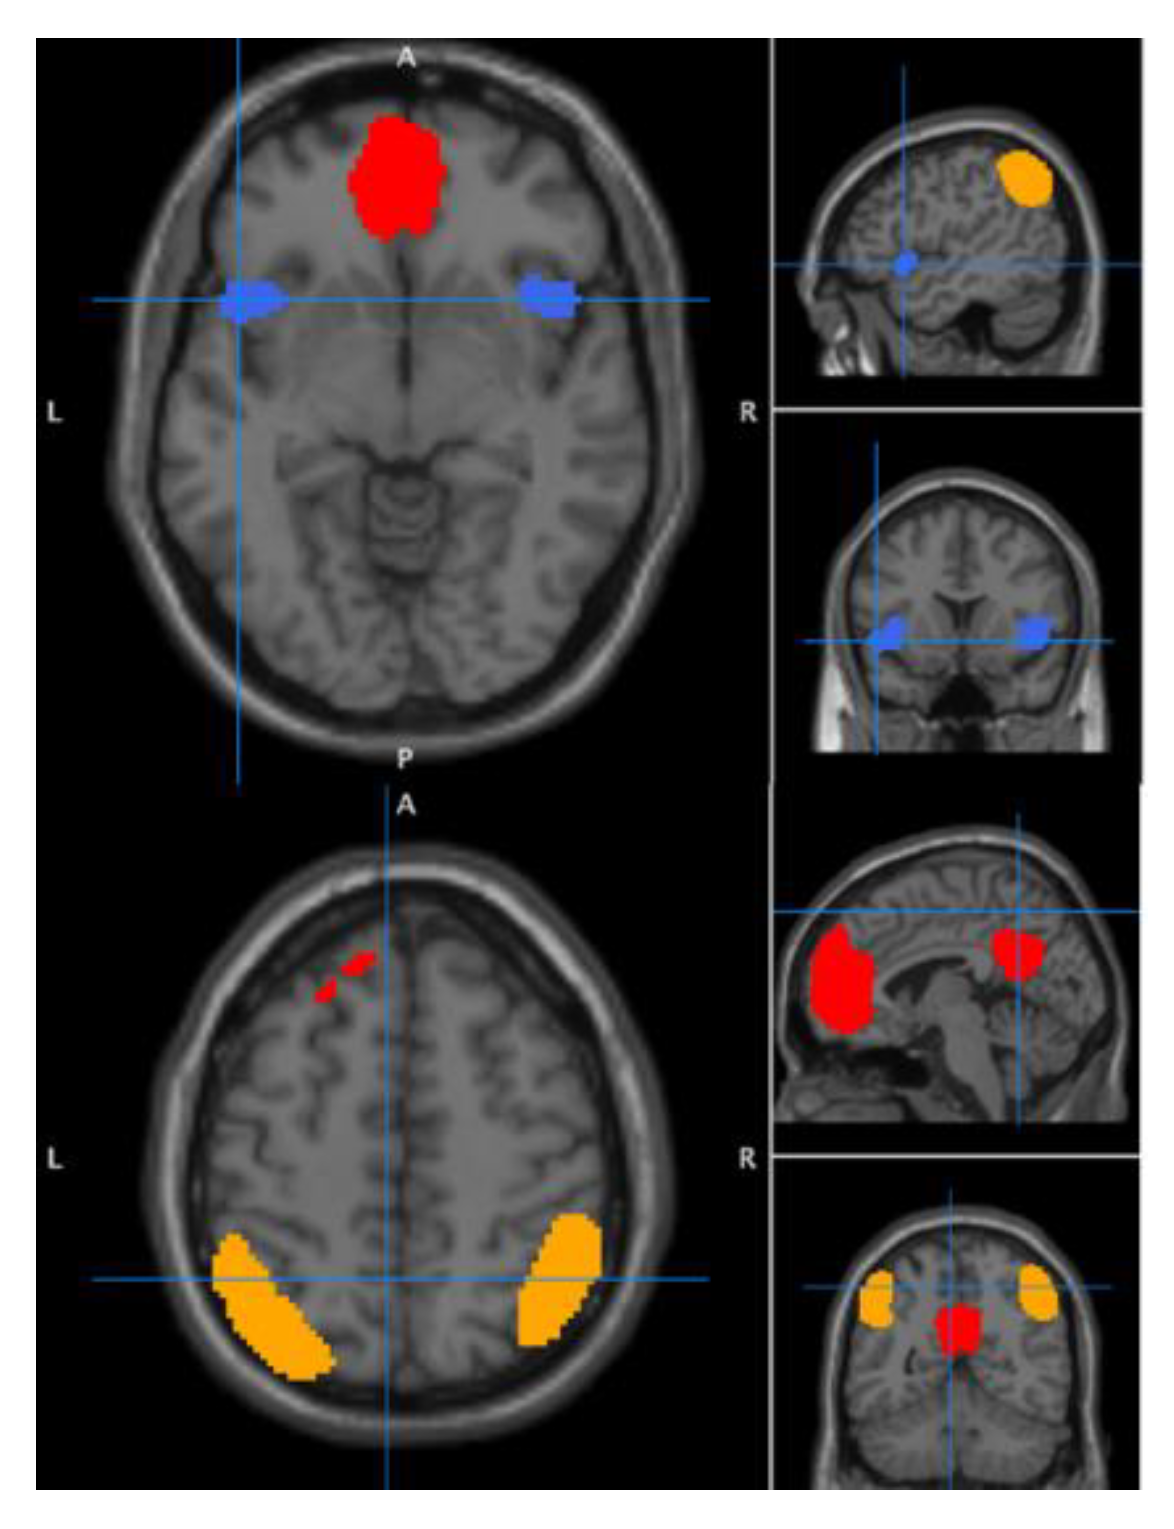

3.2. Seed-Target Tests of between and within-Group Effects

3.3. Exploration of Functional Connectivity ROI to Whole Brain